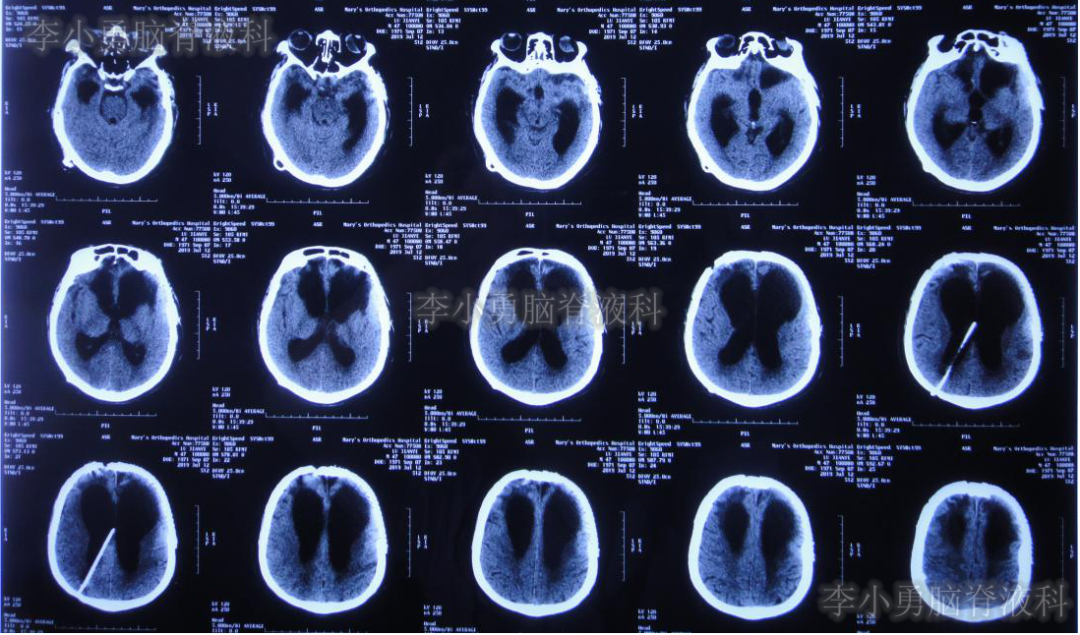

颅骨修补及脑室腹腔分流术后1周即2019年3月27日即开颅术后86天,从第2家医院直接转回第1次开颅手术的山西省某三甲医院康复科,行康复治疗;但入院当天即出现高热39.2℃,以及恶心、呕吐症状。行胸部CT,抽血化验等检查及头颅CT(图-4)后,认为均无明显异常。

图-4:2019年3月27日头颅CT

给予抗感染,营养神经等治疗,但是高热、恶心、呕吐症状仍持续10余天无好转。第3次咨询北京某三甲医院的专家后,考虑脑积水分流术后颅内感染,建议行腰椎穿刺进行脑脊液检查,结果确实有脑脊液白细胞增高。

2019年4月22日即脑室-腹腔分流术后34天,第3家医院住院第2天再次出现发热38.6℃,并行头颅CT(图-6)检查示仍为脑室引流术后状态;但胸部CT(图-7)检查示肺炎。

图-6:2019年4月23日头颅CT

虽然已显示出脑积水加重的表现,但医生仍考虑发热为肺部感染引起,因此给予抗菌素治疗2月余。但发热仍难以控制,并且患者意识也逐渐恶化至昏迷的状态,肢体活动亦明显减少。2019年7月2日(颅骨修补术+脑室-腹腔分流术后105天)复查头颅CT(图-8)示脑室进一步扩大。无奈此时再次给予腰椎穿刺,但脑脊液化验仍不支持“颅内感染”。

图-8:2019年7月2日头颅CT